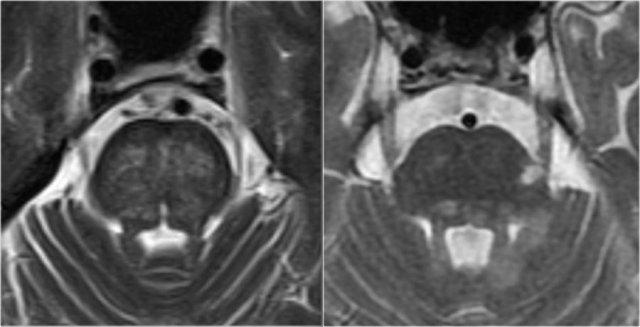

Tổn thương thân não đối xứng trong bệnh lý mạch máu nhỏ (trái) so với tổn thương MS không đối xứng điển hình (phải)

Tổn thương thân não

Trong MS, các tổn thương thân não thường có vị trí ngoại vi.

Trong bệnh lý mạch máu nhỏ, thân não có thể bị tổn thương, nhưng thường có tính chất đối xứng và nằm ở vị trí trung tâm.

Hình ảnh này minh họa sự khác biệt điển hình giữa tổn thương thân não do mạch máu so với MS (cùng hình ảnh như trên).

Hình bên trái là ảnh cắt ngang chuỗi xung T2W minh họa tổn thương thân não do mạch máu điển hình, với tổn thương trung tâm của các sợi cầu não ngang.

Hình bên phải là ảnh cắt ngang chuỗi xung T2W của thân não bệnh nhân MS, cho thấy các tổn thương chất trắng điển hình nằm ở ngoại vi, thường ở hoặc gần bó sinh ba, hoặc tiếp giáp với não thất IV.